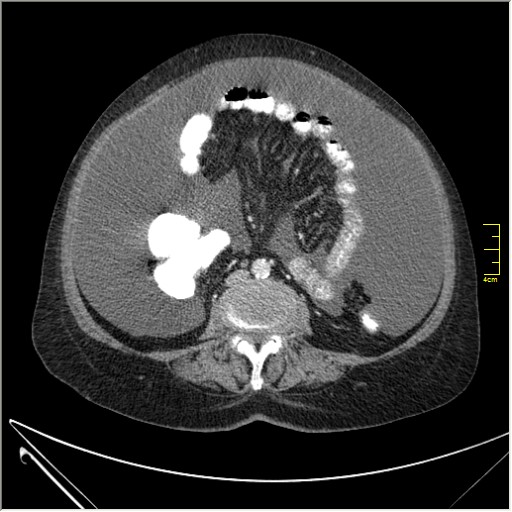

Женщина 72 года. Поступила с жалобами на вздутие живота. После осмотра хирургом, была сразу направлена на КТ брюшной полости.

Итак, асцит с объёмным образованием таза. В данном случае можно быть более конкретным, у пациентки неоплазия правого яичника с региональной лимфаденопатией (увидели?) и выраженным асцитом, характерным именно для злокачественных опухолей яичников. Пациентка оперирована ( операция Вертгейма); диагноз верифицирован: аденокарцинома правого яичника (серозная). Направлена к онкологу для дальнейшего лечения.